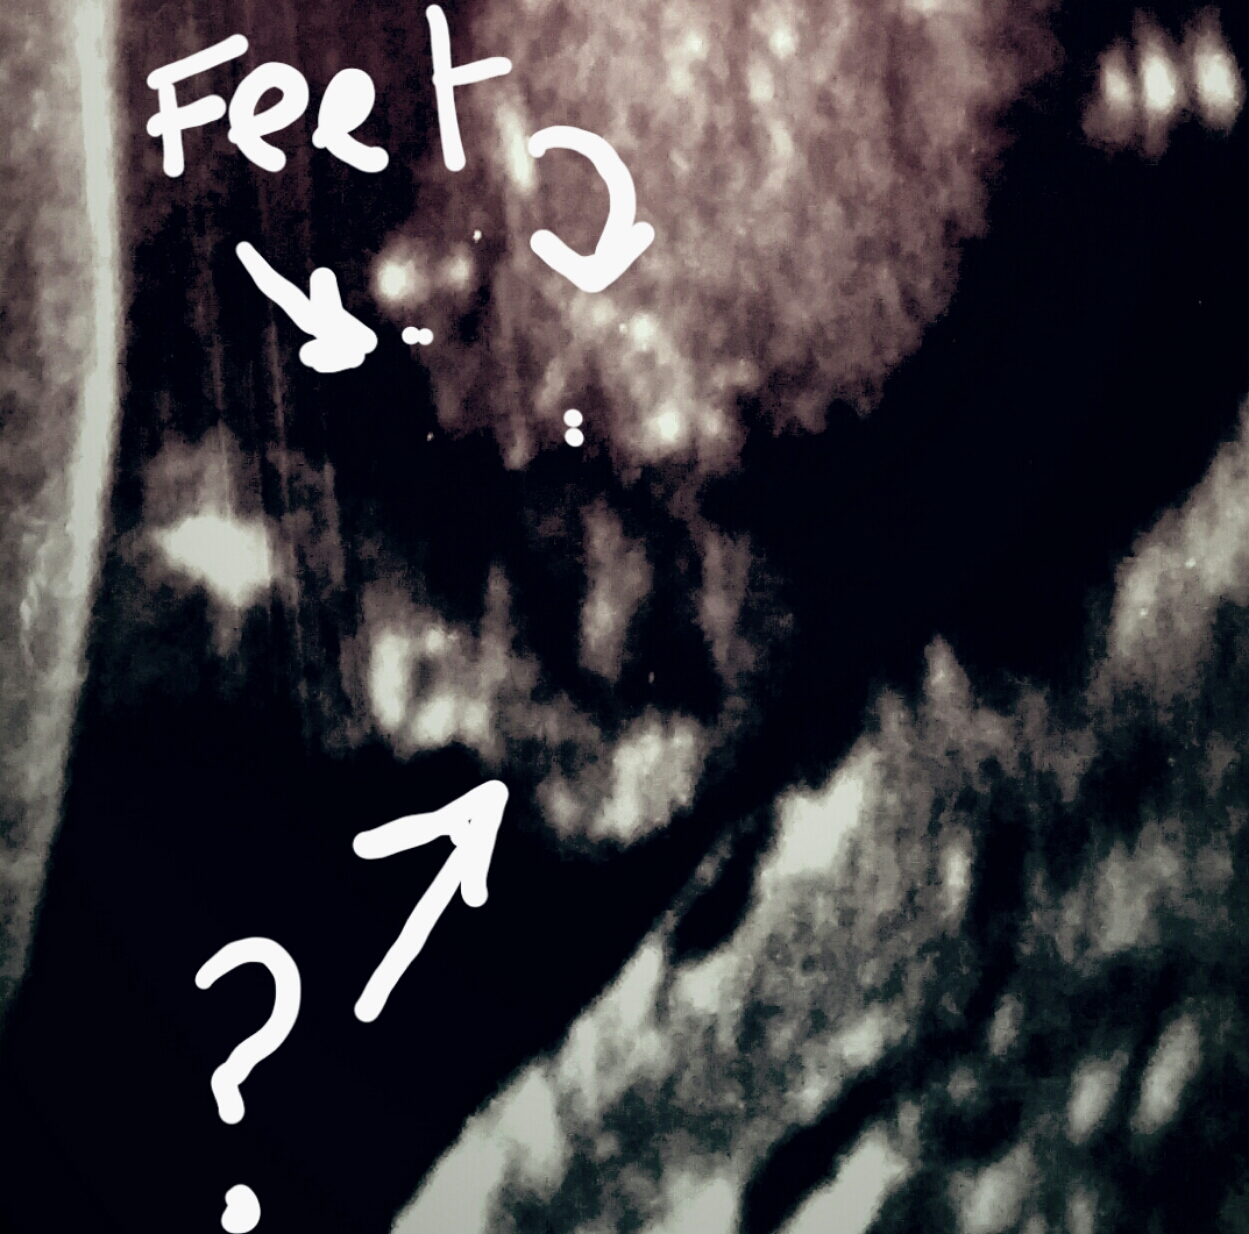

The only semi decent pic I have that would give me some idea is this one unfortunatly, Im not sure but I think that what iv put the arrow to may be its bits but not sure.

Ok, it could be a girly potty shot:

Attachment 34653